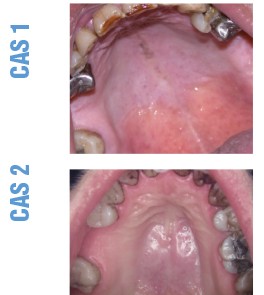

CAS 1 Motif de la consultation. Femme de 66 ans, adressée pour le diagnostic et le traitement de douleurs palatines...Us et abus des antibiotiques en endodontie (3/3)